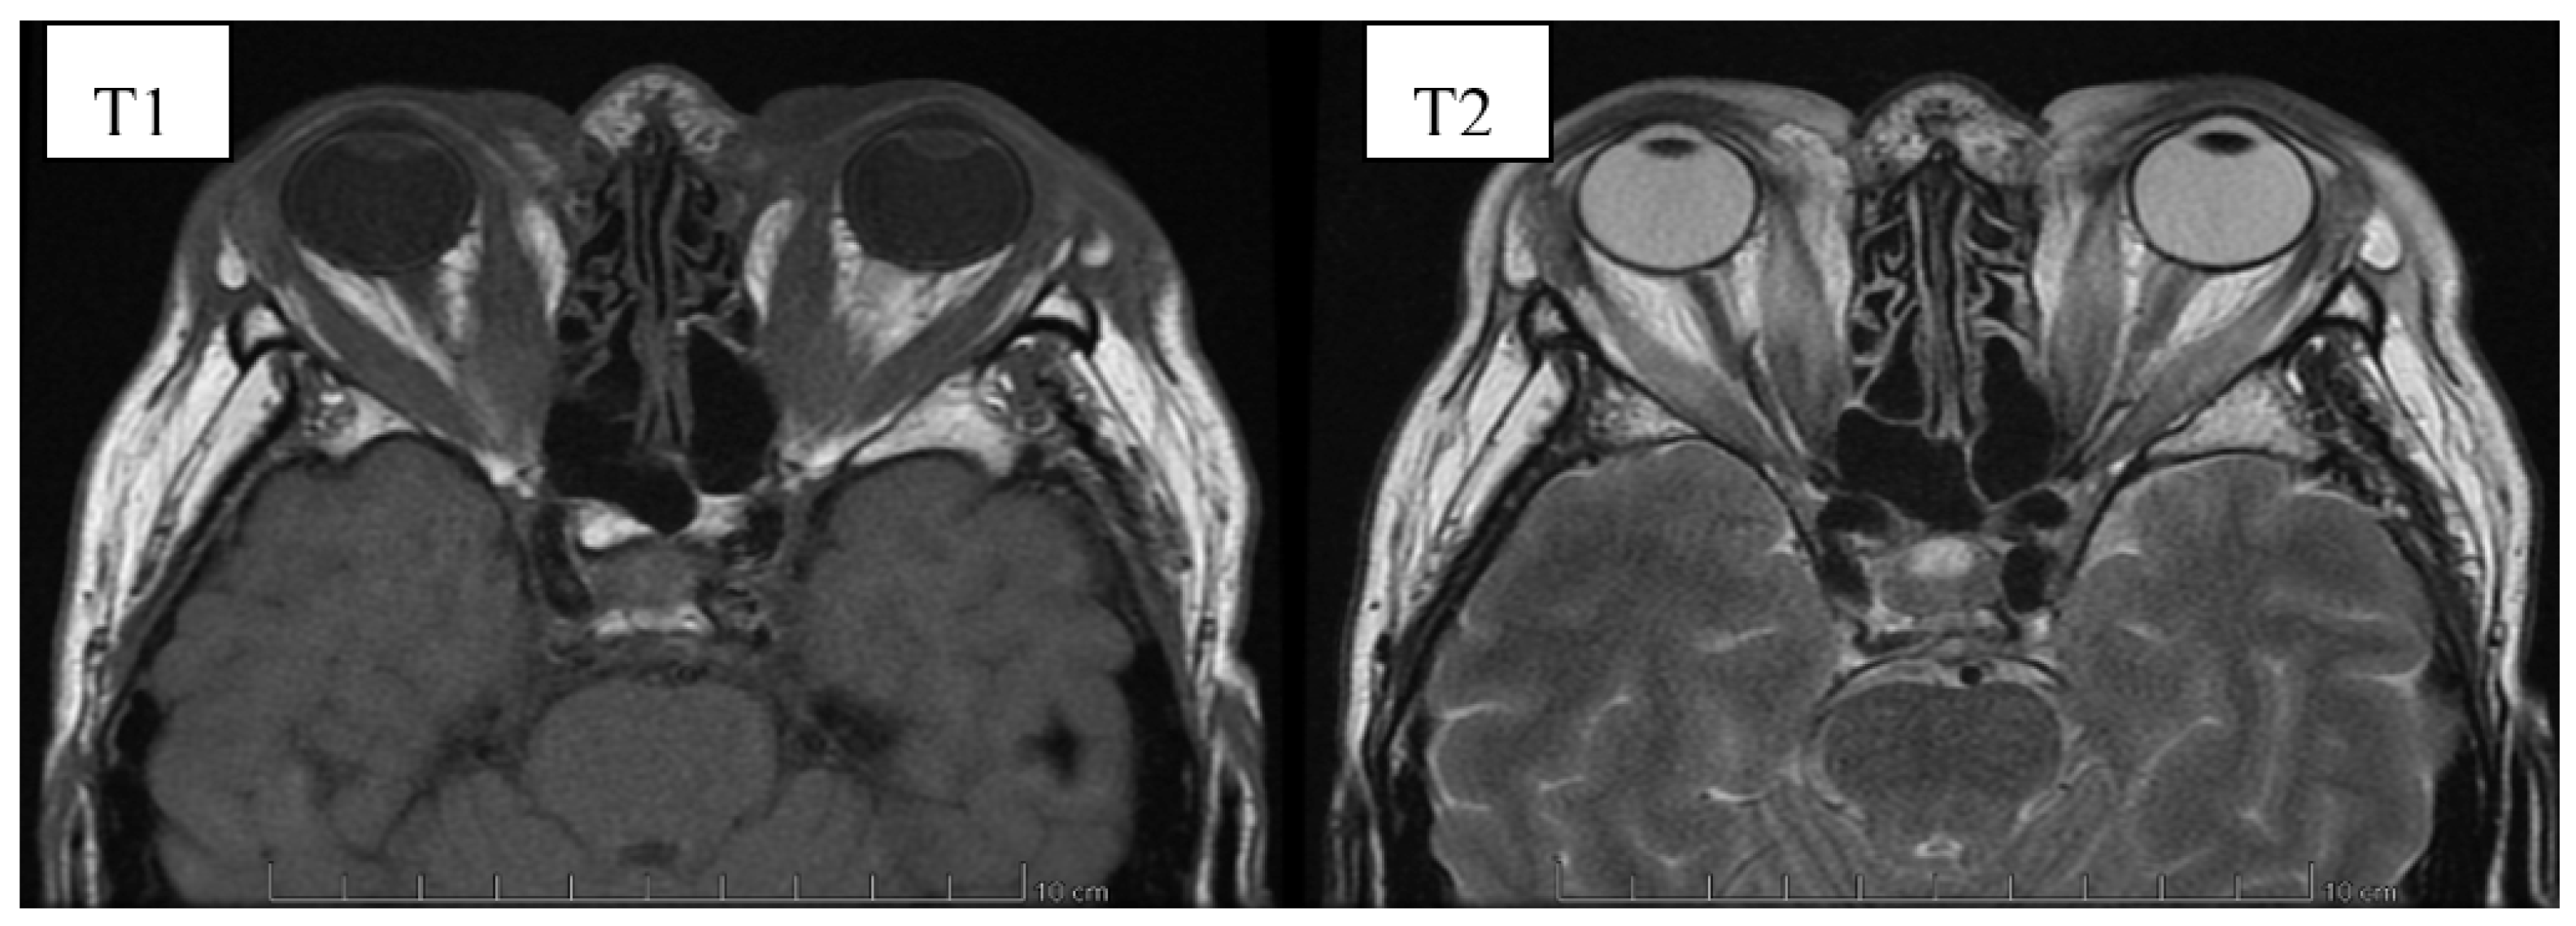

6. Image Evaluation

- Gonçalves, A.C.P.; Gebrim, E.M.M.S.; Monteiro, M.L.R. Imaging studies for diagnosing Graves’ orbitopathy and dysthyroid optic neuropathy. Clinics 2012, 67, 1327–1334. [Google Scholar] [CrossRef]

- Kahaly, G.J. Imaging in thyroid-associated orbitopathy. Eur. J. Endocrinol. 2001, 145, 107–118. [Google Scholar] [CrossRef]

- Müller-Forell, W.; Kahaly, G.J. Neuroimaging of Graves’ orbitopathy. Best Pract. Res. Clin. Endocrinol. Metab. 2012, 26, 259–271. [Google Scholar] [CrossRef] [PubMed]

- Cakirer, S.; Cakirer, D.; Basak, M.; Durmaz, S.; Altuntas, Y.; Yigit, U. Evaluation of extraocular muscles in the edematous phase of Graves ophthalmopathy on contrast-enhanced fat-suppressed magnetic resonance imaging. J. Comput. Assist. Tomogr. 2004, 28, 80–86. [Google Scholar] [CrossRef]

- Kirsch, E.; Hammer, B. Graves’orbitopathy: Current imaging procedures. Swiss Med. Wkly. 2009, 139, 618–623. [Google Scholar]